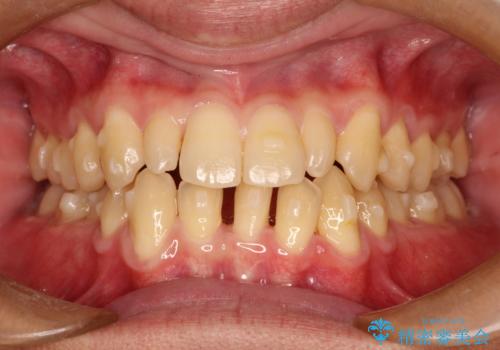

- 前歯のがたつきが気になるとのことで来院されました。

骨格的なところと、上下の歯の大きさのことを考慮して、下の前歯を1本抜歯し、インビザラインにて矯正治療することとなりました。

上の前から2番目の歯がもともと小さかったため、最後にかぶせ物を装着することで、自然な仕上がりにできました。